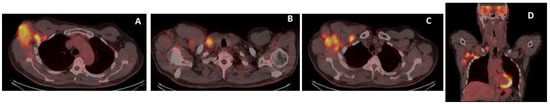

A bone marrow biopsy was performed, a diagnosis of stage-II NHL was made, and the patient underwent monoclonal antibody anti-CD30 Brentuximab Vedotin in association with CHP chemotherapy (Cyclophosfamide, Adriblastine, Prednisone) for six cycles from March to July 2022, with complete remission after three cycles (early PET). No particular signs of toxicity were observed during treatment, which was well-tolerated. The patient is on follow-up, with a good health condition and persistent complete remission, as confirmed by PET/CT restaging at the end of the treatment (Figure 6).

Figure 6.

Restaging 18-FDG-PET/CT after chemotherapy showed the complete metabolic response of all the involved sites (A–D).